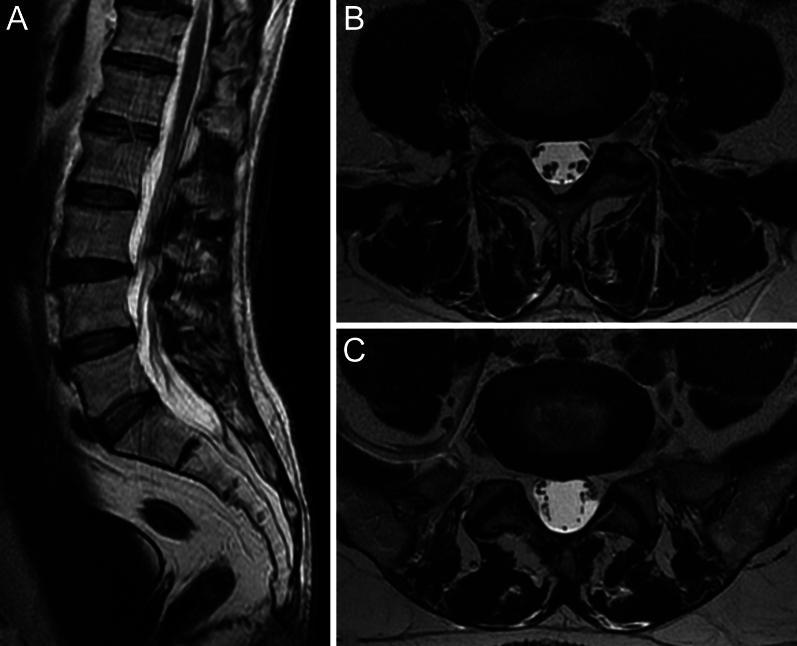

Sciatica usually results from lumbar nerve compression due to factors like disc herniations or lumbar canal stenosis. Despite its common causes, sciatic pain in a 52-year-old man following a coronavirus disease 2019 infection highlighted the importance of considering less common factors. Initially, minor disc protrusions were suspected as the cause of the symptoms, leading to the offer of surgery at another facility. The patient sought a second opinion, and our evaluation revealed a unique finding.

坐骨神经痛通常由椎间盘突出或腰椎管狭窄等因素导致的腰神经受压引起。尽管其病因常见,但一名52岁男性在感染2019冠状病毒病后出现的坐骨神经痛凸显了考虑罕见因素的重要性。最初,怀疑轻微的椎间盘突出是症状的原因,导致在另一家机构建议进行手术。患者寻求第二种意见,而我们的评估发现了一个独特的结果。